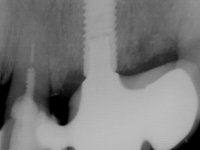

Primeira Fase

Foram feitas as extrações das raízes dos dentes 2.1 e 2.2 porque estavam a incomodar. Após 3 meses de cicatrização fez-se o exame imagiológico e estudo implantar para colocação do implante no local do 2.1.Foi colocado um implante de 4.1mm de diâmetro por 10mm de altura, colocado ao nível ósseo. Passados 2 meses após a cirurgia implantar, foi feita a segunda cirurgia para colocação de um parafuso de cicatrização. Foi feita a impressão ao implante com técnica de moldeira aberta com silicone de dupla viscosidade um mês após. No laboratório foi confecionada uma infraestrutura metálica para uma ponte de 2 elementos aparafusada ao implante. Esta infraestrutura apresentava 2 apoios palatinos para ajudar a estabilizar os dentes 1.1 e 2.3 a recuperar do traumatismo. Recuperados os dentes, os apoios poderiam ser retirados. Esta peça apresentava uma conexão interna ao implante com sistema anti-rotacional. A prova da infraestrutura foi feita em boca sendo o seu correto ajuste verificado com controle imagiológico. No revestimento da infraestrutura foi utilizada cerâmica de tonalidade coronária e gengival. Depois de verificada em boca e aprovada pelo paciente a ponte foi apertada definitivamente e o orifício de acesso obturado.